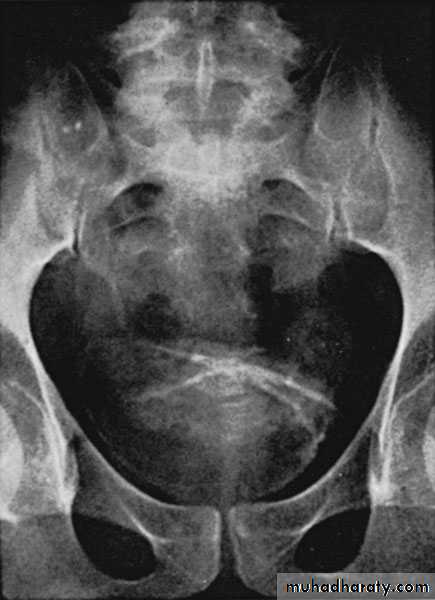

Bilateral PUJO